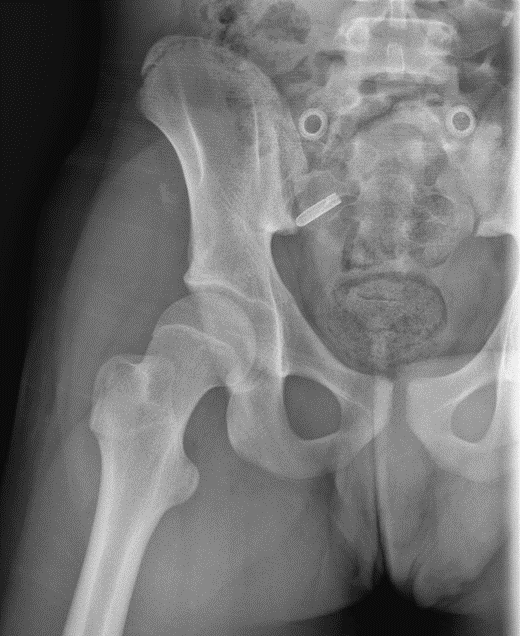

Figure 3. X-ray of the right hip 1 month post-traumatic.

Figure 4. X-ray of the right hip 8 months post-traumatic.